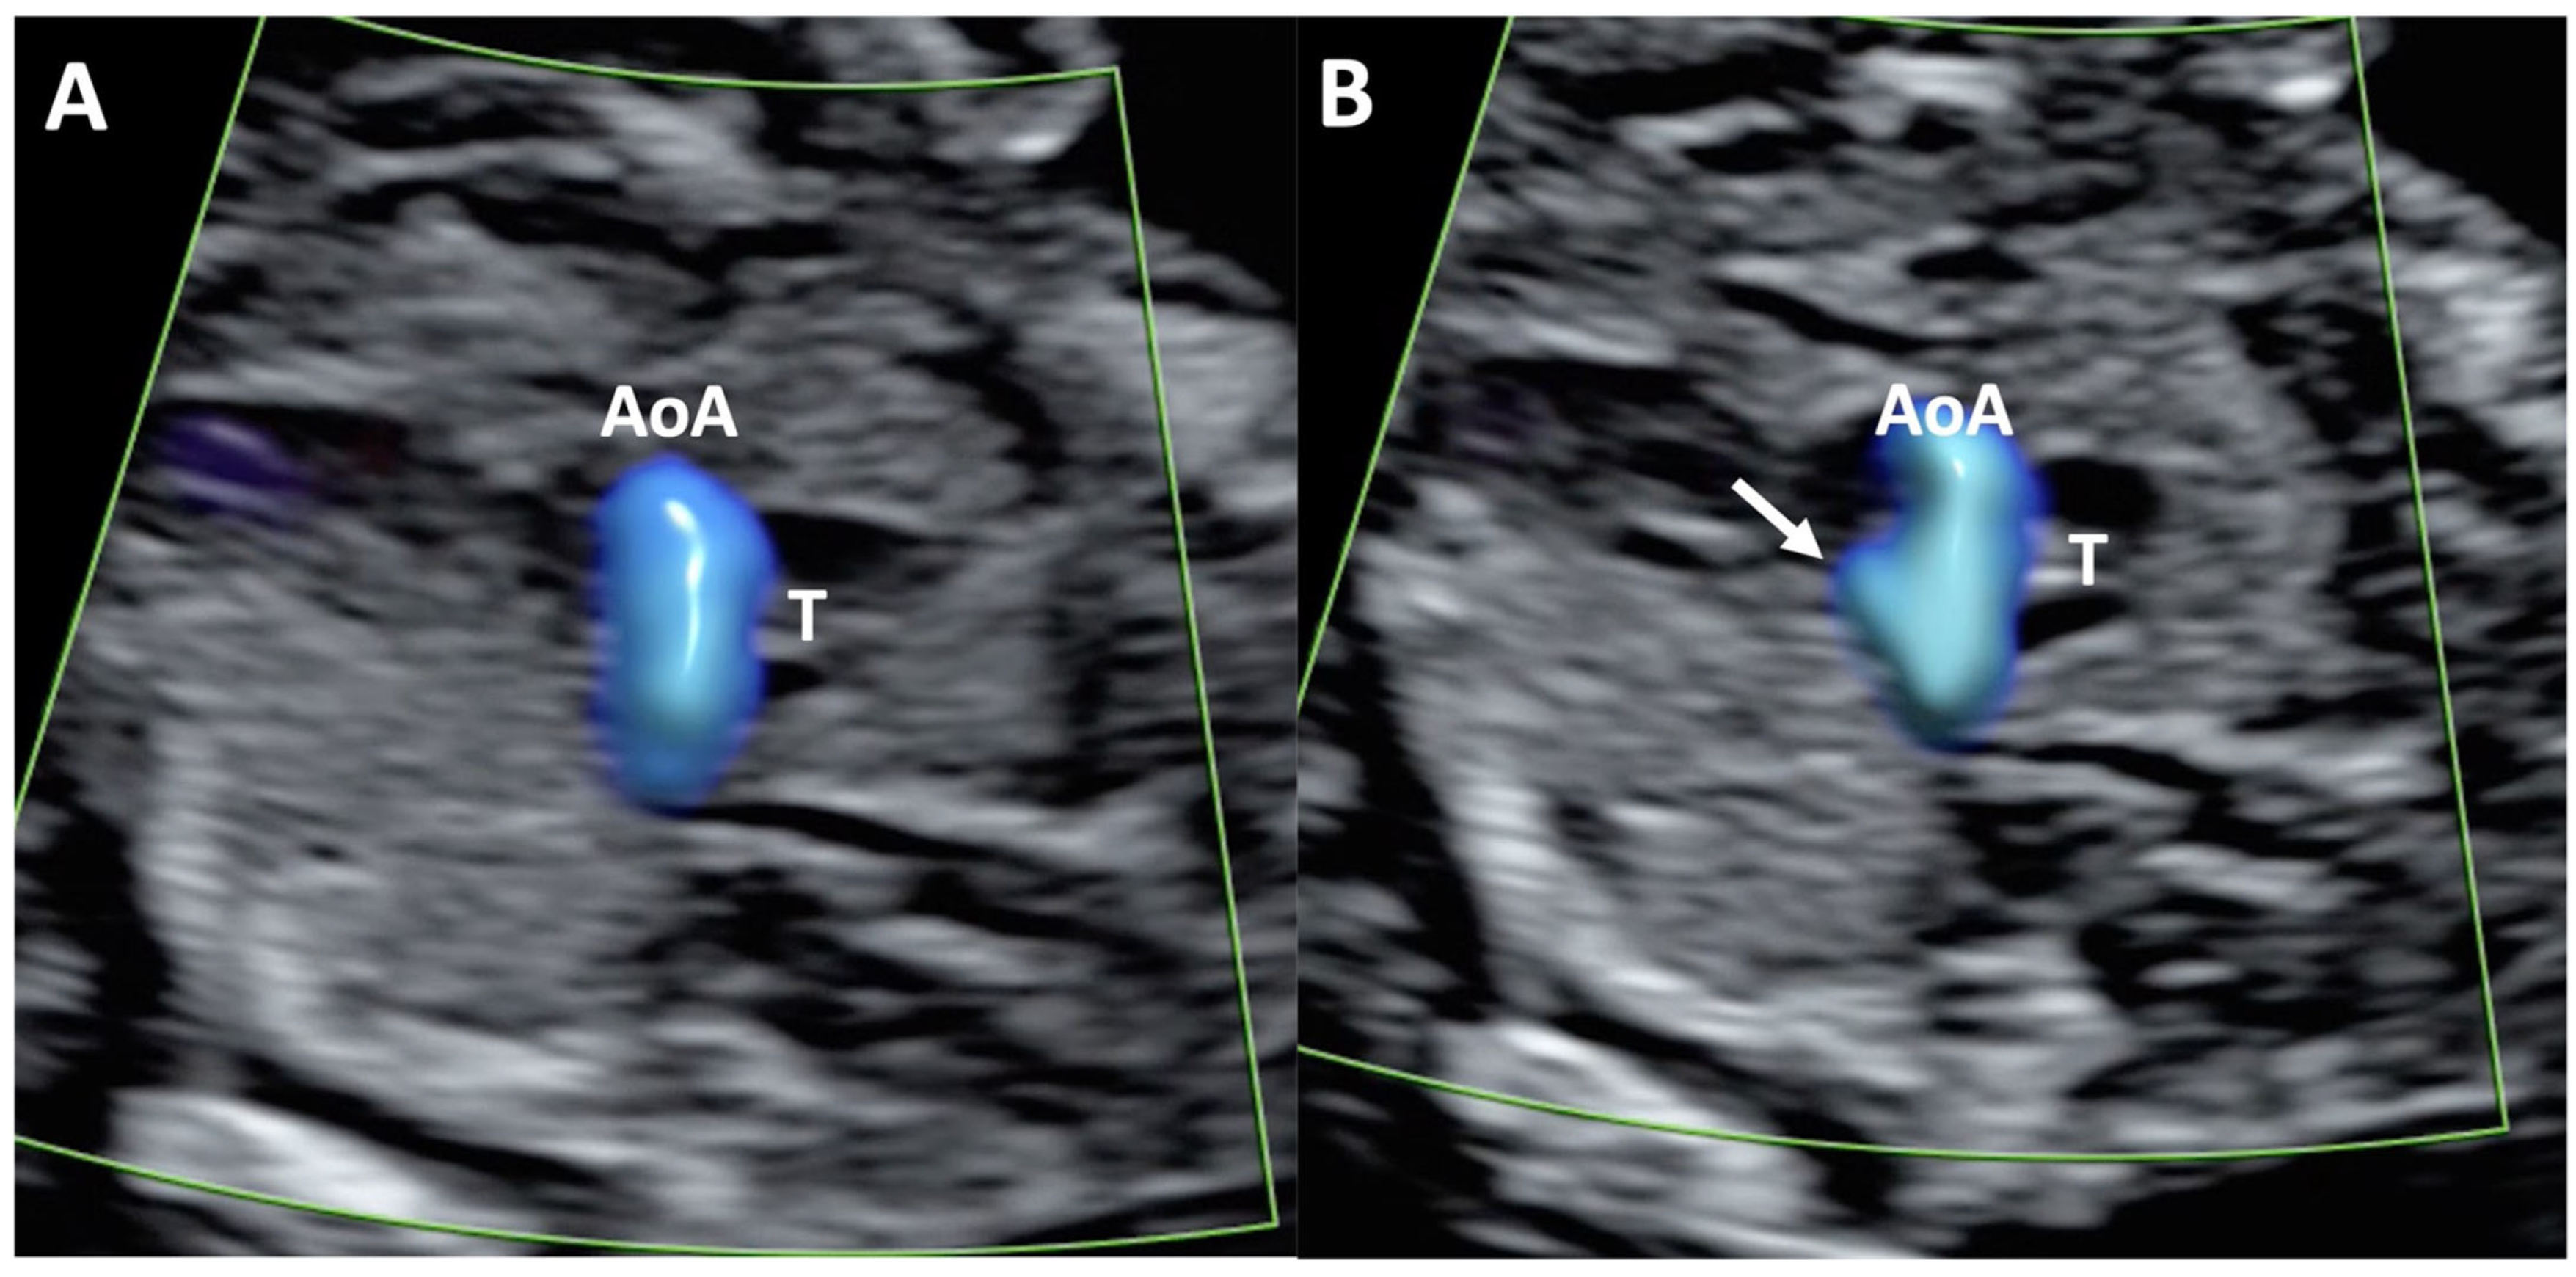

Figure 1.

Case of disagreement in the characterization of color Doppler pattern on the 3VTV between operators 1 and 2 in a case of Ebstein anomaly at 12 + 6 weeks’ gestation. (A,B) show different frames of a videoclip of the 3VTV. (A) Operator 1 observed an abnormal 3VTV pattern in terms of “abnormal vessel number”; (B) operator 2 characterized the same case as with “abnormal vessel dimensions”. AoA, aortich arch; T, trachea; arrow, small pulmonary artery.